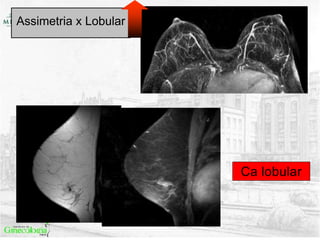

Assimetria x Lobular

• Assimetrias x lobular

• Incompatibilidade BX